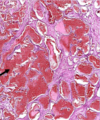

Diagnosis Describe Behavior

Hepatocellular carcinoma Section in liver which has malignant tumor formed of infiltrating trabeculae and sheets of malignant hepatocytes separated by CT. The tumor cells are polygonal Malignant